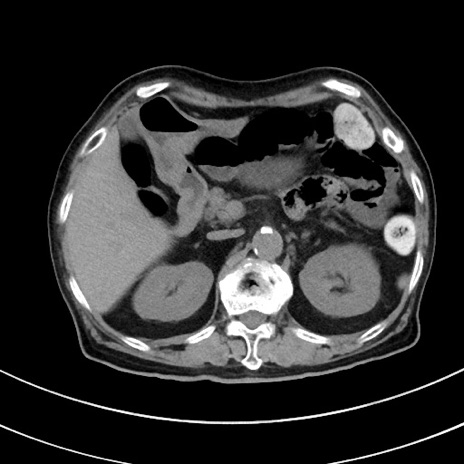

症例33(横断像)

【症例】70歳代 女性

【主訴】心窩部痛

【現病歴】延髄病変の精査・加療にて神経内科入院中。本日より心窩部痛あり。

【既往歴】虫垂炎

【身体所見】右下腹部を中心に圧痛と反跳痛あり。

【データ】WBC 10900、CRP 0.02